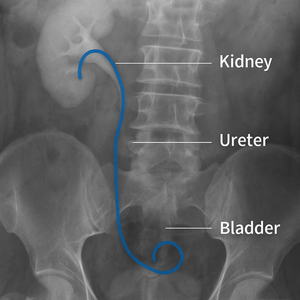

DJ STENT

Q. DJ स्टेंट म्हणजे काय? A. DJ स्टí..